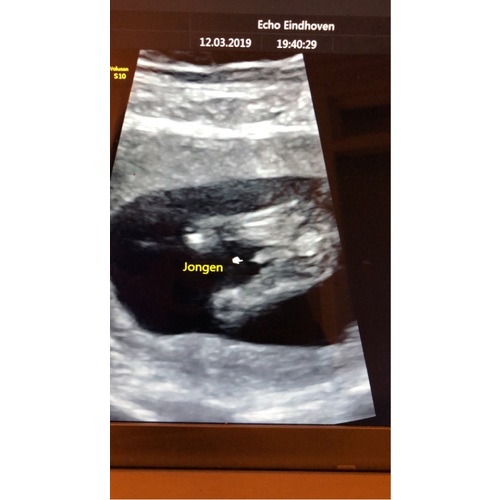

Echo met 14 weken, jongetje ( al ben ik zelf nog wat sceptisch omdat het zo vroeg was ) 🙈

6 jaar geleden

Reactie op mamavan3kids

Echo met 14 weken, jongetje ( al ben ik zelf nog wat sceptisch omdat het zo ...

Ooh maar deze is wel duidelijk idd